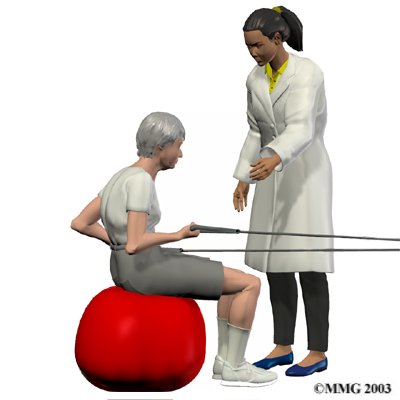

As the pain from the compression fracture begins to subside, your physical therapist at Iron City Physical Therapy will begin to focus on improving any flexibility and strength deficits you may have developed from the period of decreased activity following the compression fracture.

In addition to range of motion exercises, your Iron City Physical Therapy physical therapist will also prescribe strengthening exercises which focus on the deep abdominal muscles for overall support of the spine, as well as exercises to strengthen the back muscles which resist the forward bending of the spine. For patients with osteoporosis, it is important to include weight bearing exercise such as walking or stair climbing. Bone reacts to increase stress by producing more bone, which increases its overall strength. The added stress of simple weight bearing activities therefore works to encourage stronger bones. Your physical therapist may also prescribe exercises for you using light weights for the same reason of encouraging the build up of overall bone strength.

At Iron City Physical Therapy we believe that education for our patients is of utmost importance therefore discussions on how to improve and maintain your posture will be a large focus of our treatment. Your physical therapist will discuss proper body mechanics when moving in order to keep your back in safe positions and avoid extra strain near the fracture as you go about your work and daily activities. We will discuss positions you use when sitting, lying down, standing, and walking as well as safe body mechanics with lifting, carrying, pushing, and pulling. We will also educate patients with osteoporosis on the proper techniques for simple daily activities such as coughing or sneezing, which due to the forceful flexion involved, can result in another compression fracture in those with particularly frail bones. Falling can also easily result in fractures of osteoporotic bones so balance activities may be added to your home program to decrease the likelihood of a fall occurring. The goal of rehabilitation at Iron City Physical Therapy is for you is to improve your posture, body mechanics, strength, and flexibility so as to avoid future injuries.